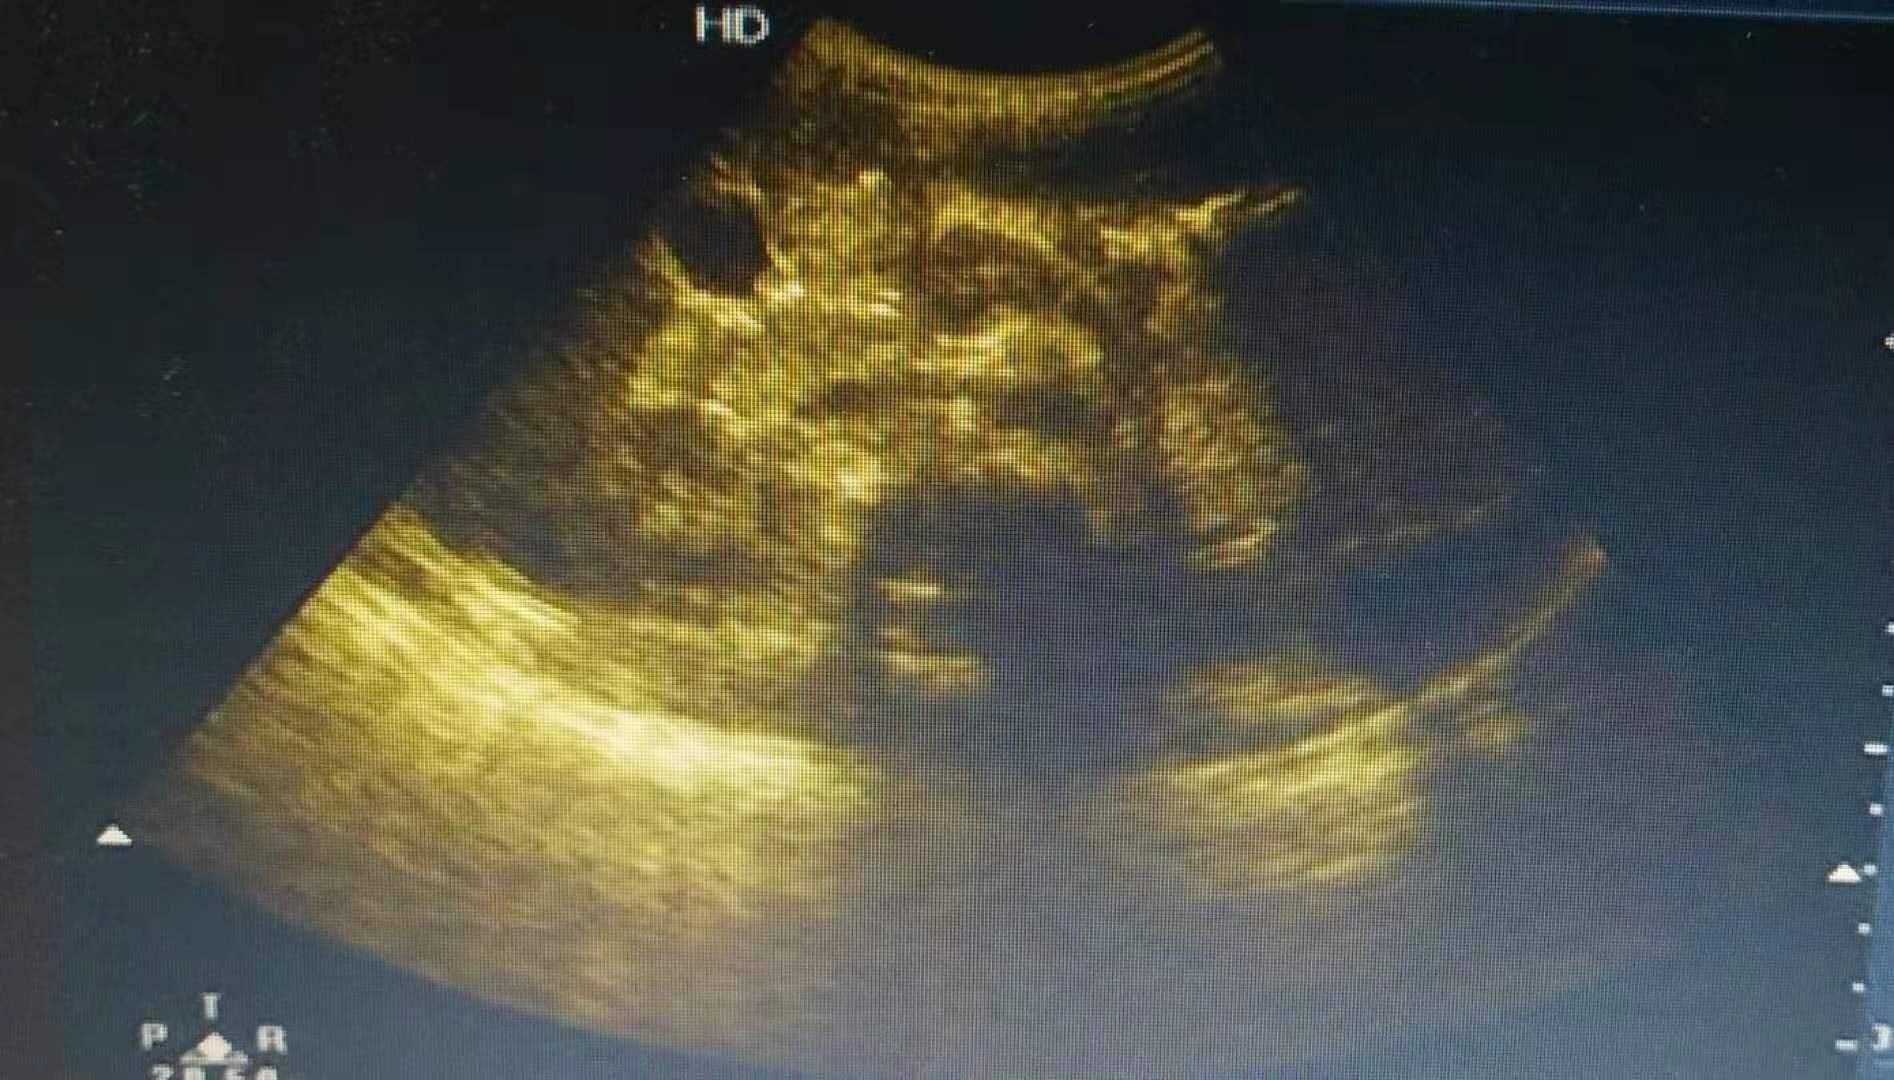

患儿有发热,腮腺肿大,轻度触痛,*丸睾**肿胀、压痛, 伴有阴囊皮肤红肿。查血淀粉酶:淀粉酶(AMS)800U/L;血清C-反应蛋白、PCT、肝肾功能未见异常,血常规五分类(BRT):白细胞数目4.5X10^9/L,淋巴细胞百分比80%,彩超提示腮腺、*丸睾**肿大,跟家长交流孩子病情,细菌感染指标不高,考虑病毒感染引起可能性大,孩子目前诊断流行性腮腺炎继发出现*丸睾**炎了,可予干扰素雾化抗病毒治疗,患儿胃口差,适量补液营养支持治疗。患儿*丸睾**疼痛明显,用固定带固定*丸睾**于腹壁并口服布洛芬止痛,经治疗后患儿症状明显改善。同时叮嘱家长避免酸性食物,多吃流质食物为主。注意口腔清洁,避免继发感染。